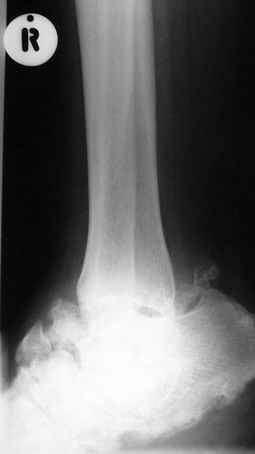

Отдельные случаи мелореостоза отличаются друг от друга по степени и форме склеротических участков; каждый случай

представляет свои неповторяемые особенности. В более тяжелых случаях поражения нижней конечности захвачена и

соответствующая половина таза, при локализации в верхней конечности - часть лопатки. Из парных костей поражается,

как правило, только одна: это большеберцовая или малоберцовая кость, лучевая или локтевая кость, но никогда не

обе кости одновременно. Мы наблюдали изолированные поражения не только периферических, но и ближе к туловищу

расположенных костей, например, бедра без вовлечения в процесс голени, или половины таза с соответствующей

половиной нижних поясничных позвонков и проксимальной части бедренной кости. Другими словами, в редких случаях

объем изменений совсем не возрастает по направлению к.периферии. В самых редких случаях в какой-то ничтожной

степени в процесс может быть вовлечен череп (часть нижней челюсти). Поражения ребер мы ни разу не наблюдали.

Измененный корковый слой, а также уплотненные эпифизы и мелкие губчатые кости приобретают плотность слоновой

кости. Корковый слой утолщается как в сторону костномозгового канала (эндостальная форма), в большей или меньшей

степени суживая его, так и наружу (периосталь-ная форма), возвышаясь над нормальным уровнем кости и увеличивая

этим ее наружный диаметр. Поверхность "наплывов" слегка волниста, с гребневидными возвышениями и углублениями, но

всегда резко конту-рируется. Склеротические полосы и ленты бывают чаще всего сплошными, но нередко они

прерывисты, расслоены. Иногда наблюдается некоторое удлинение костей и их небольшая дугообразная деформация, а

подчас и наоборот - очень незначительное укорочение. Это зависит, надо думать, от участия энхондрального хряща,

раздражения или торможения его функции. Костная ткань в соседстве со склеротическими полосами и островками

сохраняет нормальный рисунок или часто слегка поротична, так что граница между затемненными склеротическими

лентами и костным фоном очень резка. Иногда в мягких тканях таза или области плечевого пояса развиваются

неправильные шаровидные плотные костные массы, а при прогрессировании болезни подобные островки появляются и в

окружности суставов, которые сами по себе особых изменений не представляют. Патологические переломы при

мелореостозе не описаны. Мы также по собственному опыту и по литературным данным не знаем озлокачествления при

мелореостозе. Течение болезни вообще вполне доброкачественное и общее предсказание благоприятное.